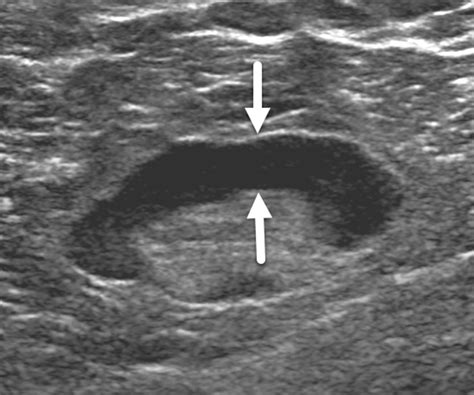

To understand what is a sonogram from a technical perspective, it helps to look at how the machinery functions. Unlike X-rays, which use radiation, sonograms rely on safe, high-frequency sound waves. A handheld device called a transducer is moved over the skin of the abdomen or inserted into the vagina. This transducer emits sound waves that travel through the body and bounce off tissues, organs, and the fetus, returning as echoes. A computer then interprets these echoes and translates them into real-time images on a monitor.

The sonographer will then move the transducer firmly across your belly. You may feel slight pressure, but it should not be painful. As they scan, you will see grainy, black-and-white images on the screen. While these might look like indistinct shapes to the untrained eye, the professional performing the exam is trained to identify specific structures and measurements.